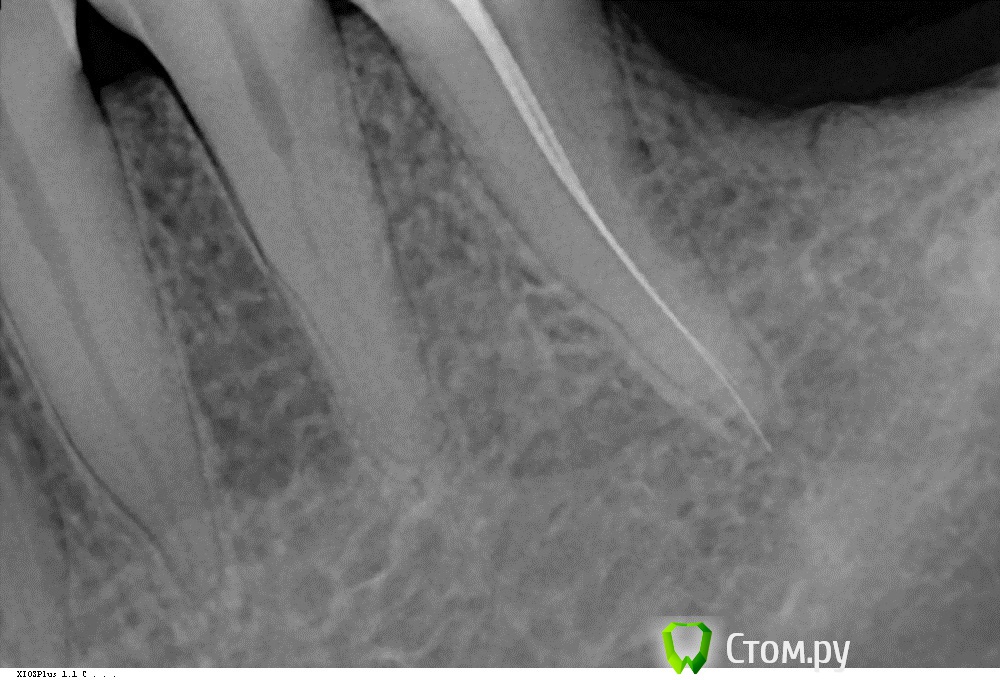

volosyatka Опубликовано 16 марта, 2014 Поделиться Опубликовано 16 марта, 2014 (изменено) Пациент с пульпитом 35. В зубе два канала, которые разделяются где-то в средней трети корня. То есть вход один, канала два. На соседнем зубе 34 аналогичный вариант. Никак не могу пройти в этот второй канал. Положила кальций. Что посоветуете? Изменено 16 марта, 2014 пользователем volosyatka Ссылка на комментарий

Магас Опубликовано 1 апреля, 2014 Поделиться Опубликовано 1 апреля, 2014 Пациент с пульпитом 35. В зубе два канала, которые разделяются где-то в средней трети корня. То есть вход один, канала два. На соседнем зубе 34 аналогичный вариант. Никак не могу пройти в этот второй канал. Положила кальций. Что посоветуете?пациент.jpgмне кажется или на снимке файлы расходятся в нужных направлениях Ссылка на комментарий

Аслан Опубликовано 2 апреля, 2014 Поделиться Опубликовано 2 апреля, 2014 Мне кажется, или там вообще нет второго канала? А есть снимок в развороте и без инструментов? А еще больше Вам поможет кт ) Ссылка на комментарий